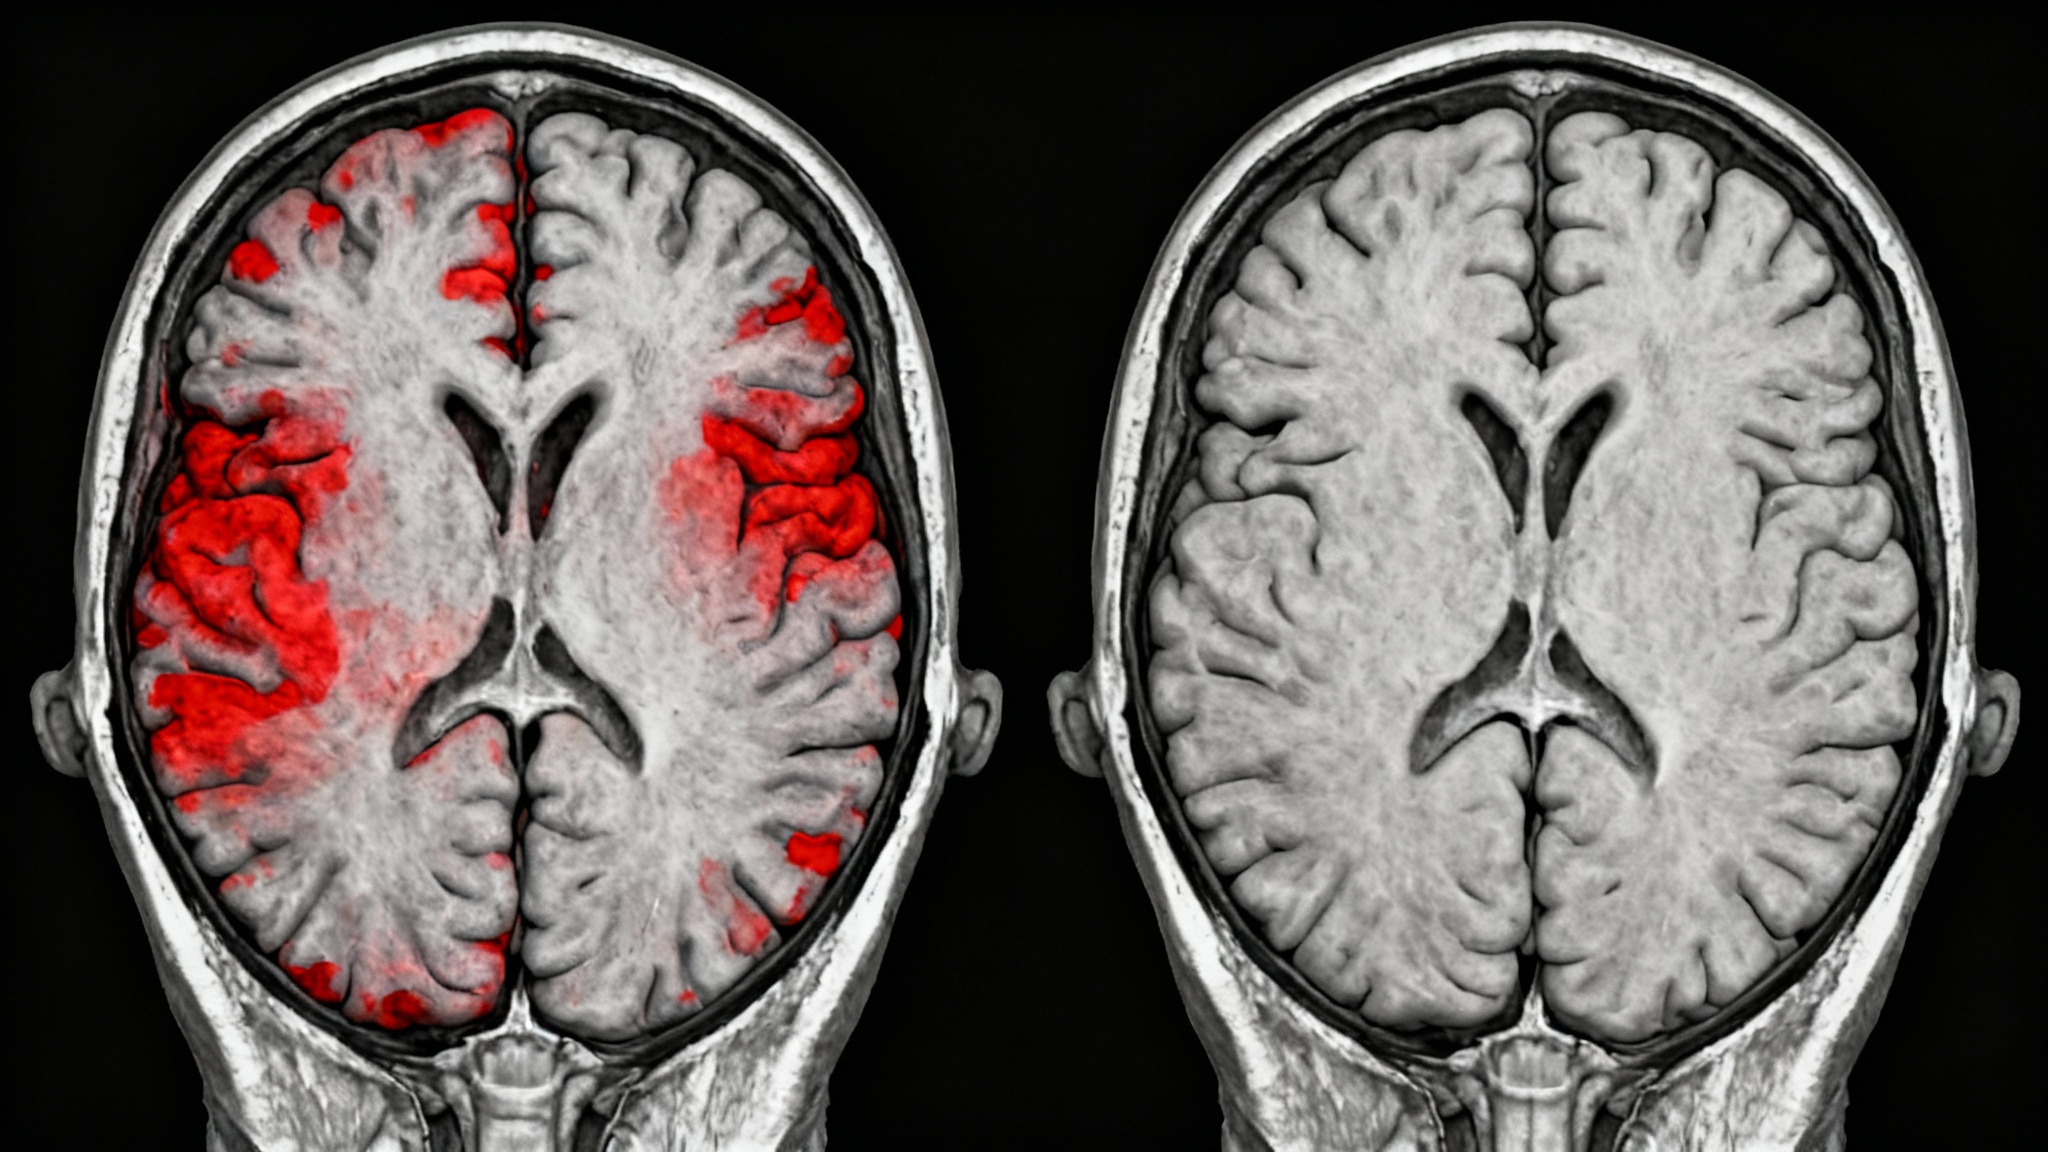

Parkinson : le cerveau des femmes serait-il secrètement protégé par leurs hormones ?

Face aux maladies neurodégénératives, sommes-nous tous égaux ? Une étude canadienne vient de jeter un pavé dans la mare en suggérant que les femmes pourraient bénéficier d’une protection naturelle contre la maladie de Parkinson. Publiés dans Nature Communications, ces travaux révèlent une différence biologique frappante qui pourrait bien orienter la recherche vers de toutes nouvelles pistes de traitement.